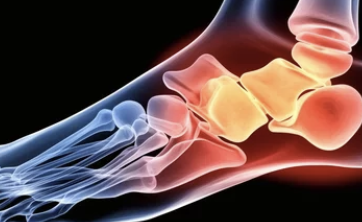

1️⃣ 족저근막염

- 가장 흔한 발바닥 통증 원인

- 발뒤꿈치부터 발가락까지 이어진 족저근막에 미세 손상이 생겨 염증 발생

- 특징: 아침에 첫 발 디딜 때 극심한 통증, 걸으면서 점차 완화

- 원인: 오래 서 있는 직업, 과체중, 잘못된 신발 착용